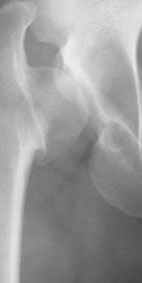

Dear All,This 27 year old presented to a colleague, about 2 years back, with complaints of bilateral hip pain. He was treated symptomatically, but now has increasing pain, and walking distance is being limited.

On examination, he has got a lordotic gait, Trendelenberg negative, bilaterally, hip movements fairly good, with no FFD.X-rays are attached.Kindly give your opinions regarding management and future prognosis.Thanks and regardsMuhammad Amin Chinoy FRCS

It appears that this patient has bilateral congenital hip displasia, as presented on the radiographs. As shown, the problem involves both sides of the hip joint: the acetabulum and proximal femur.

This patient is noted to have a very vertical joint surface orientation, as well, with retroversion of the acetabulum.

In a hip with normal version, (on discussion list) Hip Pain (Dr.Kullerkann) the lines connecting the anterior and posterior acetabular wall as seen on an AP radiograph usually intersect at one point near the superior and lateral portion of the acetabulum. As an example of an abnormal hip, a patient with a retroverted acetabulum will show the figure 8 pattern, with the two shadows crossing over the femoral head. In this particular patient, again it appears that there is a significant amount of retroversion of the acetabular wall, as the anterior wall appears to be more anteriorly displaced than in a normal hip.